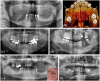

Bone replacement might have been practiced for centuries with various materials of natural origin, but had rarely met success until the late 19th century. Nowadays, many different bone substitutes can be used. They can be either derived from biological products such as demineralized bone matrix, platelet-rich plasma, hydroxyapatite, adjunction of growth factors (like bone morphogenetic protein) or synthetic such as calcium sulfate, tri-calcium phosphate ceramics, bioactive glasses, or polymer-based substitutes. All these substitutes are not suitable for every clinical use, and they have to be chosen selectively depending on their purpose. Thus, this review aims to highlight the principal characteristics of the most commonly used bone substitutes and to give some directions concerning their clinical use, as spine fusion, open-wedge tibial osteotomy, long bone fracture, oral and maxillofacial surgery, or periodontal treatments. However, the main limitations to bone substitutes use remain the management of large defects and the lack of vascularization in their central part, which is likely to appear following their utilization. In the field of bone tissue engineering, developing porous synthetic substitutes able to support a faster and a wider vascularization within their structure seems to be a promising way of research.